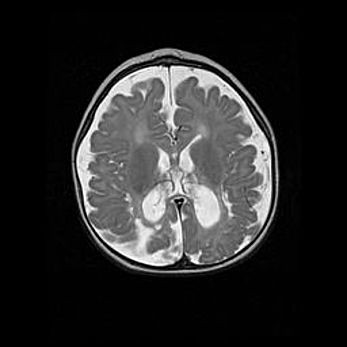

Наружная гидроцефалия с возможной атрофией височных областей.

Возраст: 28 дней

Вес: 3670 г

Пол: мужской

Окружность головы: 38 см

Срок гестации: 40 недель

Гидроцефалия головного мозга у новорожденных – это заболевание, которое характеризуется скоплением избыточного количества спинномозговой жидкости в желудочковой системе головного мозга в результате затруднения её перемещения от места выработки к месту поглощения в кровеносную систему или вследствие нарушения абсорбции. При открытой наружной форме гидроцефалии у новорожденных расширяются и переполняются субарахноидные пространства.

При нормотензивных  формах,  которые,  как  правило,  являются  следствием  перенесенных ишемических  повреждений  паренхимы  мозга,  возможно  сочетание микроцефалии  с нормотензивной гидроцефалией. В основе данных изменений лежит атрофия больших полушарий с преимущественной  локализацией  в  лобно-височных  областях.